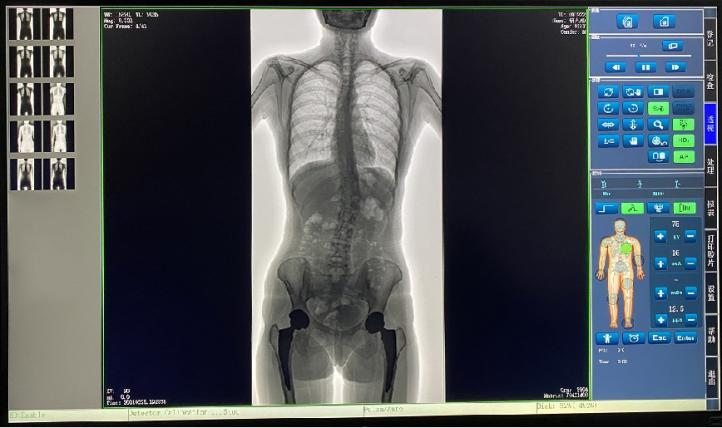

普愛醫(yī)療新推出一款動態(tài)平板DR-PLX8600,這款產品可攝影、可透視、可造影,臨床適用范圍廣泛,可滿足不同臨床拍攝需求。一體式的機架,擺位簡單快捷,不僅融合了市面上17英寸動態(tài)DR的所有功能,還有獨具特色的超大動態(tài)視野范圍,給臨床應用帶來醫(yī)療診斷價值,降低醫(yī)院設備投入成本,獲得更大收益。

1.專為大視野臨床應用打造的平板動態(tài)DR,圖像不拼接,有效簡化影像科室檢查流程,提高診斷精度,降低患者吸收的輻射劑量。

2.解決了拼接圖像存在密度不均勻,拼接處圖像配準和放大效應等問題,輻射劑量小。